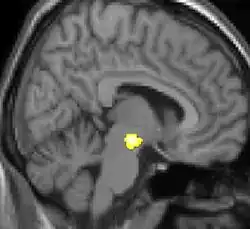

| La morphométrie voxel par voxel (VBM) montre les différences structurelles des zones du cerveau | ||

Les images par tomographie à émission de positron indiquent les régions du cerveau qui sont activées lors de la douleur, par rapport aux périodes sans douleur. Elles montrent les régions du cerveau qui sont toujours actives durant la douleur en jaune/orange (appelé "matrice-douleur"). La zone au centre (dans les trois vues) est spécifiquement activée uniquement pendant la crise. Les photos sur la ligne du bas (effectuées par VBM) montrent les différences structurelles entre les patients souffrant d'AVF et des personnes saines : seulement une partie de l'hypothalamus est différente[50],[51].